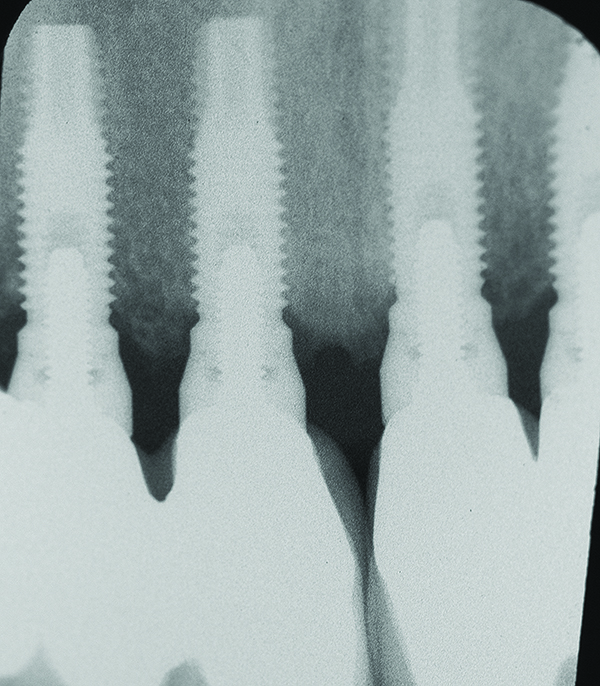

Fig 7 through Fig 14. Periapical radiographs of a 62-year-old woman who received a fixed porcelain-fused-to-metal reconstruction supported by abutments by internally connected dental implants. Fig 7 through Fig 10 are at initial prosthesis placement: mandibular site Nos. 30 and 29 (Fig 7); mandibular site Nos. 26, 25, and 23 (Fig 8); mandibular site Nos. 23 and 21 (Fig 9); mandibular site Nos. 21 through 19 (Fig 10). Fig 11 through Fig 14 are 11 years later (2013) and show excellent preservation of the vertical bone levels around the implants: mandibular site Nos. 30 and 29 (Fig 11); mandibular site Nos. 26 and 25 (Fig 12); mandibular site Nos. 25 and 23 (Fig 13); mandibular site Nos. 20 and 19 (Fig 14). It is interesting to note that in the mandibular right posterior quadrant there is a matched pair, ie, an external hex dental implant (No. 30) adjacent to an internally connected dental implant (No. 29). The bone levels around each of these designs are well-preserved at the 11-year follow-up.